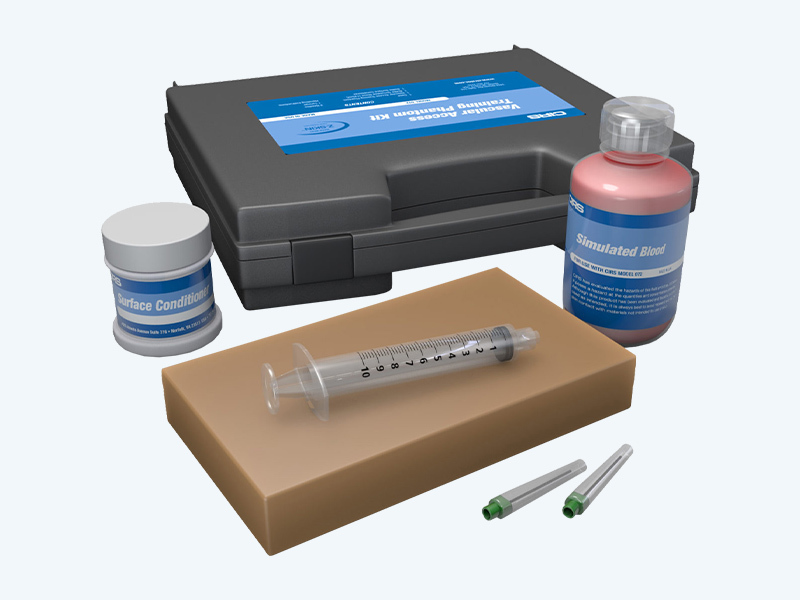

Vascular Access Training Phantom

- Demonstrate and practice various insertion techniques

- Teach ultrasound scan techniques

- Experiment with new procedures and evaluate new devices

Specifications

Dimensions |

100 mm x 175 mm x 30 mm |

Weight |

2 lbs (0.7 kg) |